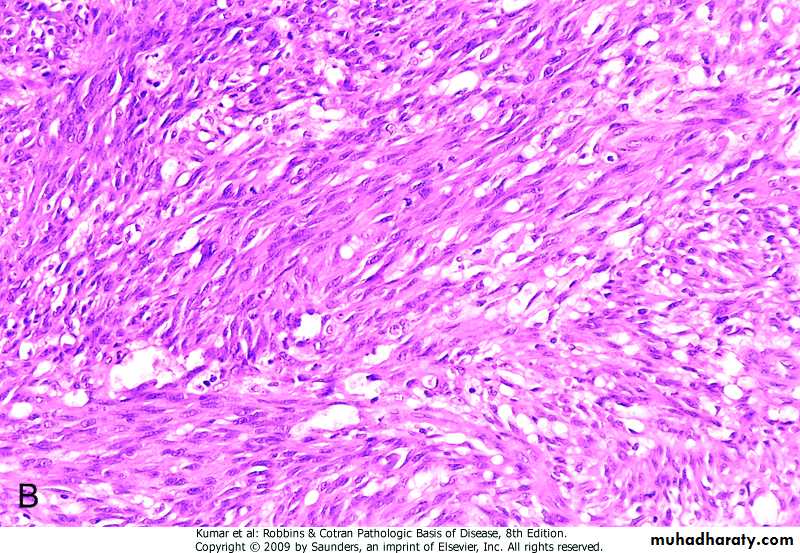

Histologically: proliferating spindle cells, slit like vessels, extravasated RBC

nodular stage, demonstrating sheets of plump, proliferating spindle cells and slit like vascular spaces.